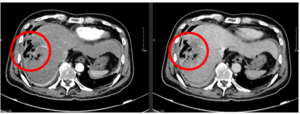

Case lâm sàng: Điều trị ung thư trực tràng trung bình di căn gan tại Trung tâm Y học hạt nhân & Ung bướu, Bệnh viện Bạch Mai

Case lâm sàng: Điều trị ung thư trực tràng trung bình di căn gan tại Trung tâm Y học hạt nhân & Ung bướu, Bệnh viện Bạch Mai GS.TS. Mai Trọng Khoa, PGS.TS. Phạm Cẩm Phương, Ths. Phạm Minh Lanh, BSNT. Nguyễn Thị Kim Ngọc. ...